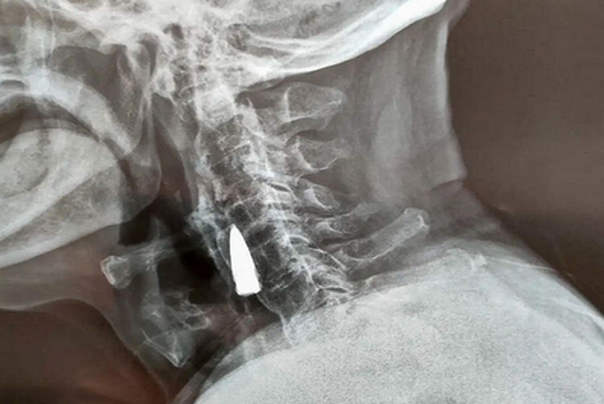

Nakon što su čuli za njegov pad, lekari su preporučili rendgen, kako bi se uverili da nije pretrpeo ozbiljno oštećenje vrata ili neke kosti. Tako je umesto nekog očekivanog preloma, rendgenski snimak otkrio strano telo u vratu čoveka, koji će kasnije biti identifikovan kao stari metak.!

Sam Džao procenjuje da mu je metak bio u vratu od 1944. godine kada ga je pogodio dok je prelazio reku. Metak je navodno ušao kroz levu stranu nosa, probušio mu gornju vilicu i izbio mu zube pre nego što mu se zaglavio u vratu. Ipak, ovo je samo njegova neka teorija

Nakon pregleda rendgenskih snimaka, doktori su rekli Žao Heu i njegovoj porodici da je metak bio blizu nekih velikih krvnih sudova i da je, pošto mu nije izazvao nikakve probleme, najbolje da ga ostave unutra. Ratni veteran se složio.